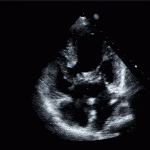

- Cleft AV Valve

- LVOT Obstruction (“Gooseneck Deformity”)

- Aortic valve positioned anteriorly and farther from the apex than the mitral valve (normally equidistant from apex).

- Long LVOT can obstruct, this is known as the “Gooseneck Deformity”